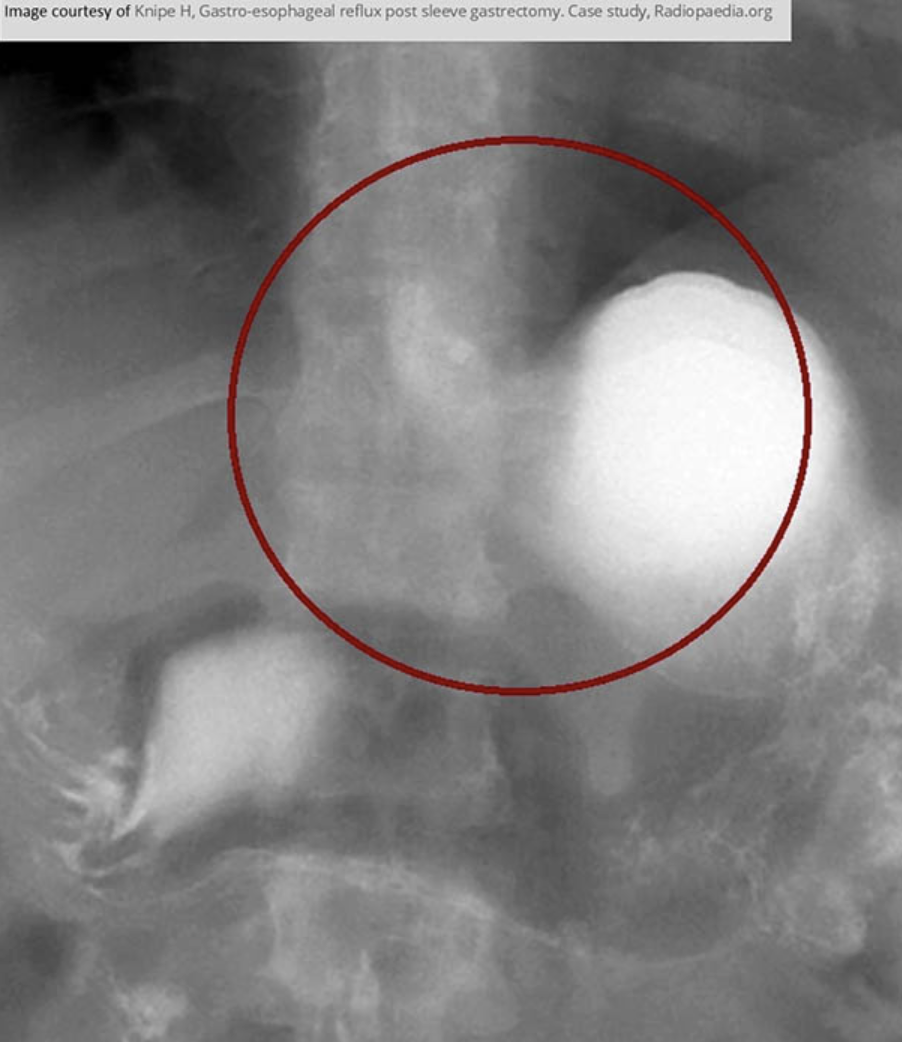

RA of GERD

Barium Swallow with UGI procedure is the standard for assessing GERD

*As GERD progresses, its appearance changes on imaging*

this image is early stage

advanced stage of GERD

Obvious narrowing of the lower esophagus due to reflux. Notice the erosion.